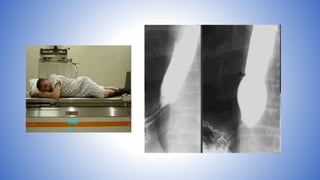

• Take one overhead film (14" x

17", 125 kVp) of the abdomen

with patient in prone position.

• Take oneoverhead film (14" x 17", 125 kVp) of the abdomen with patient in prone position.